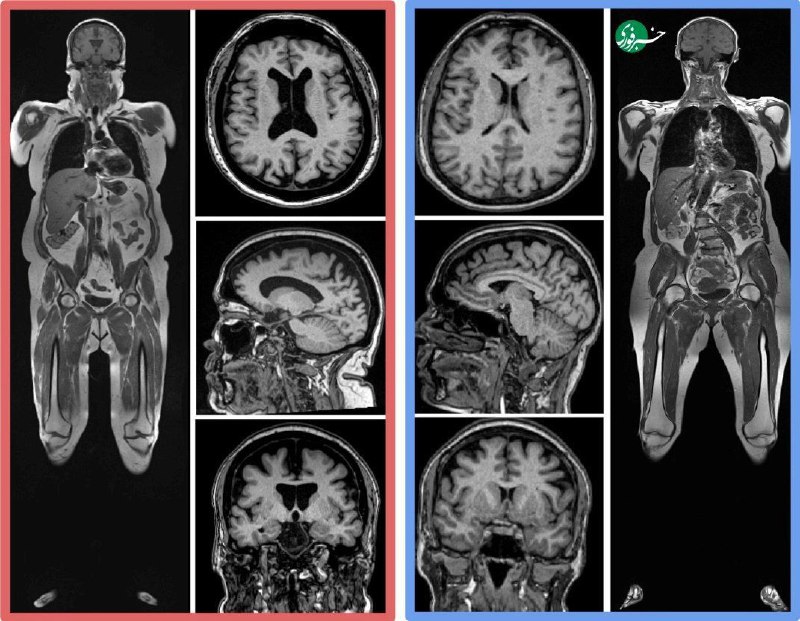

📷جوانی مغز: عضله بیشتر، چربی شکمی کمتر

🔹سیروس راجی، دانشیار رادیولوژی Ùˆ مغز Ùˆ اعصاب دانشگاه واشنگتن، در مطالعه‌ای جدید اعلام کرد: بدن‌های سالم‌تر با توده عضلانی بالاتر Ùˆ چربی Ø§ØØ´Ø§ÛŒÛŒ (Ø´Ú©Ù…ÛŒ پنهان) کمتر، مغزهای جوان‌تر Ùˆ سالم‌تری دارند.

🔹بنابراین، عضلات Ùˆ کاهش چربی Ø§ØØ´Ø§ÛŒÛŒØŒ بهترین راه برای کند کردن پیری مغز Ùˆ کاهش خطر بیماری‌هایی مانند آلزایمر است.